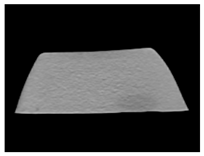

2. Materials and Methods

3. Results